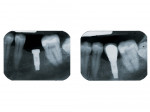

Un implant dentaire est une racine artificielle placée par le chirurgien-dentiste dans l'os alvéolaire de l'un des maxillaires en remplacement de la racine d'une dent extraite et servant de support à une prothèse.

Sa forme est généralement cylindrique ou légèrement conique, ressemblant à une vis, en titane ou en zircone, avec une connexion au niveau supérieur, à l'emplacement de la gencive, pour permettre la pose d'un élément prothétique par vissage ou scellement.

Son diamètre varie entre 3 et 5mm et sa longueur entre 8 et 15mm.

Le choix se fait en fonction de l'emplacement, de la quantité d'os disponible, et des éléments anatomiques environnants à partir d'un examen radiologique et scanner de la zone à implanter.